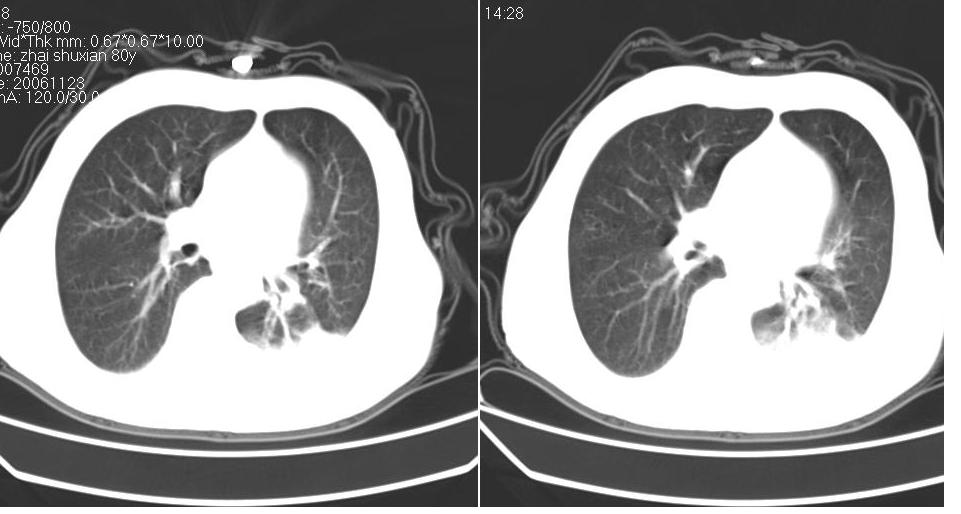

左下肺体积缩小,密度增高,见片增密影。边界模糊,见支气管充气像,肺门纵隔无异示,心脏气管左移,左侧胸腔少量积液。考虑肺部感染伴部分肺不张[有脑梗塞病史坠积性肺炎可能]

1、左肺下叶后基底段炎症并膨胀不全。

2、左侧胸腔积液。

3.两肺慢支改变。

左下肺体积缩小,密度增高,并见大片状致密影,边界模糊,其内见支气管充气像,肺门纵隔无异常,心脏气管左移,左侧胸腔少量积液。考虑:左肺炎性病变伴不张。

左肺下叶感染,肺膨胀不全,左胸腔积液,不能排除结核性病变